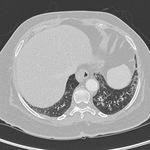

A. Portable upright chest x-ray before aspiration; B. Chest x-ray 1 hour after aspiration, showing bilateral diffuse alveolar infiltrates, worse at the bases on the right side

From the personal collection of Dr S. Murgu and Dr H. Colt, University of California at Irvine Medical Center